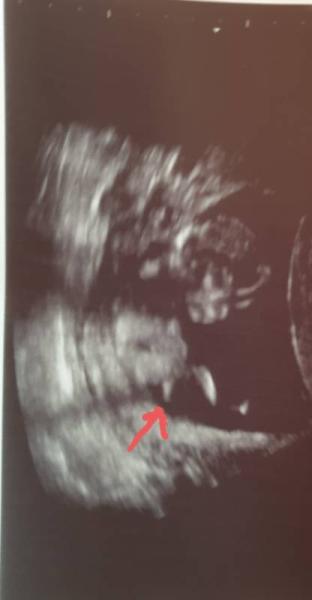

Hallo ihr Lieben, Ich hatte gestern in 14+1 Ultraschall und bin mit folgendem Bild nach Hause gegangen. Darauf sieht man deutlich was wegstehen, ist das ein Penis? Wenn ja dann finde ich ist er riiiesig. Mein Gyn hat zum Geschlecht gar nichts gesagt, und ich hab mir das Bild auch erst daheim genau angeschaut. Es ist mein erstes Kind und ich bin einfach nur neugierig. Also was würdet ihr sagen ist da auf dem Bild zu sehen? Freue mich auf eure Antworten. Lg

Danke für deine Antwort, ich habe nun auf dem Bild mit einem Pfeil markiert was ich meine. Lg

Das wird der zweite Oberschenkel sein. Ein Baby penis ist nicht so groß, da sieht man mehr den Sack, als den penis. So war es bei mir auch vor zwei Wochen.

Das ist kein Penis, sondern das zweite Bein :-)

Vielen lieben Dank für eure Antworten, da ist wohl meine Fantasie mit mir durchgegangen